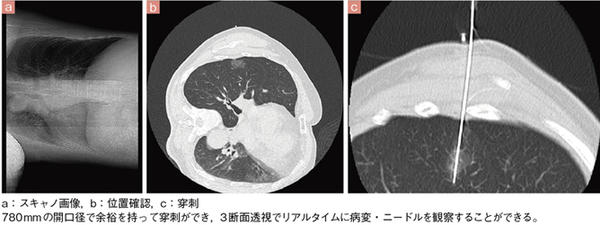

■症例1 CT透視(側臥位)

ハードウエアの進化としては,ガントリの開口径が従来機種よりも60mm広がったことも重要な要素であるが,これについても臨床上でのメリットが生まれている。三田助教は,IVRでのアクセス性の良さを説明する。

「開口径が780mmに広がったことで,CTガイド下での生検でも穿刺がしやすくなりました。被検者の体位も側臥位での撮影ができるようになり,大きなメリットだと感じています。また,ガントリの前面と背面のデザインを変え,背面側のガントリ長を長くすることで,Aquilion ONEでは検査ができなかった閉所恐怖症の方の撮影ができるなど,被検者にとっても負担の少ない装置だと言えます」